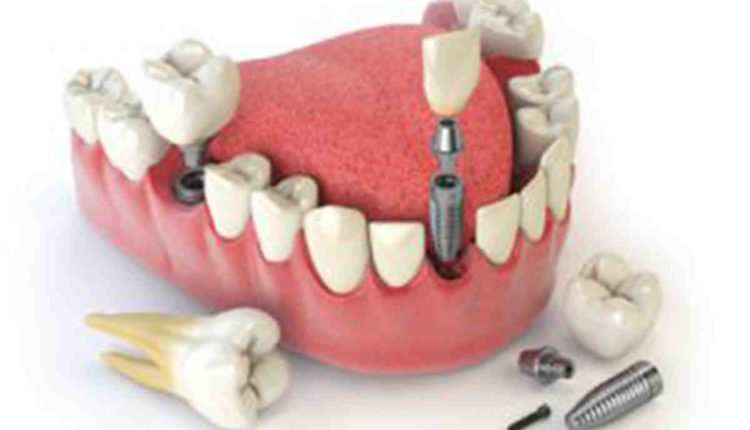

Dental implants can last a lifetime. If you have missing teeth, talk to your dentist about your options. There are several dental treatments that may be right for you. And while dental implants may be the most expensive of these options, they are certainly worth the investment!

What is the success rate of dental implants? A dental implant is a surgical component that interfaces with the jaw bone or skull to support a dental prosthesis, such as a crown, bridge, denture, facial prosthesis, or to act as an orthodontic anchor. To see also : How much do you have to put down for dental implants. 90%-95% was reported as the 10-year implant success rate.

A failed dental implant is easily removed with local anesthesia. If an implant needs to be replaced, they will remove it and gently clean the area. If the bone is intact around the area of the removed implant, no bone graft is needed.

As mentioned above, dental implants last an average of 25 years. There are many reasons why implants can last less or longer than this average lifespan. Read also : Who does dental implants in decatur, tx. These reasons are discussed below. People with good oral hygiene will have their implants longer.

The risks and complications you are taking for dental implants include infection, damage to other teeth, delayed bone healing, nerve damage, prolonged bleeding, jaw fractures, and more. If you’re willing to take those risks, dental implants may be right for you.

We recommend dental implants because:

- Dental implants last a lifetime.

- Dental implants are easy to care for.

- Dental implants prevent bone loss in the jaw.

- Dental implants may require additional procedures.

- Dental implants are expensive.

- Dental implants require surgery.

How many teeth can be attached to an implant?

An implant is rarely used to replace multiple teeth alone, but it can be combined with another to replace up to six teeth. This means that an implant alone can support a maximum of three artificial teeth.

Can a dental implant hold 2 teeth? In some cases, a single dental implant may be used to replace 2 adjacent teeth. This usually occurs in the front areas of the mouth due to the narrower width of these teeth and also because these teeth are usually subjected to less forces when compared to the molar teeth at the back of the mouth.

How many implants do you need for a bridge?

Dental bridges for dental implants Depending on how many teeth need to be replaced, enough implants need to be installed to support the teeth to be replaced. Usually 2 implants can replace 3-4 teeth. And 4-6 implants can replace a full set of upper or lower teeth. This is called full mouth and All on 4 dental implants.

How many teeth can one implant hold?

Depending on the condition of the person’s gums and jaw, sometimes a single implant can be placed to support two adjacent teeth. Most commonly, multiple implants are used to anchor fixed or removable partial bridges.

How long does a dental implant procedure take? The procedure itself takes 1 to 2 hours and the healing time is 3 to 6 months. During this time, the titanium alloy implant (the same material used in joint replacement) will heal and fuse with the surrounding bone tissue. No other load-bearing medical implant has such fast healing or recovery times.